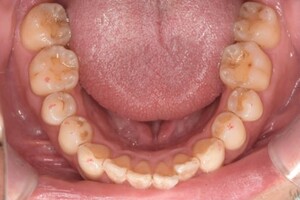

Before

After

基本情報

| 年齢・性別 | 70歳・男性 |

|---|---|

| 主訴 | 虫歯治療、定期検診 |

| 治療内容 | スケーリング |

| 治療期間 | 60分 |

| 治療費 | 1,500円(保険診療) |

| リスク・副作用 | 知覚過敏、出血 |

| 治療方針 | 今回は歯肉縁上歯石を除去しました。今後はSRPを行い、定期的にクリーニングをしていきます。 |

| 担当者所見 | 歯石を除去して歯根面が露出したことにより、知覚過敏が起こりやすいことをお話ししました。再びプラークや歯石がつかないようにセルフケアの重要性をお伝えしました。 |